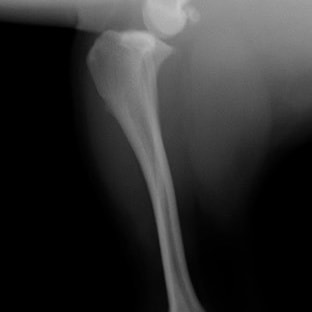

術前左後肢側面像

術後左後肢側面像

手術前後のTPA(脛骨高平部の角度)を測定しています。

約29°から約10°へ矯正されています。

術前のTPAは左後肢33.1°右後肢26.8°でしたがTPLO実施により左後肢5.5°右後肢12°に矯正されました。